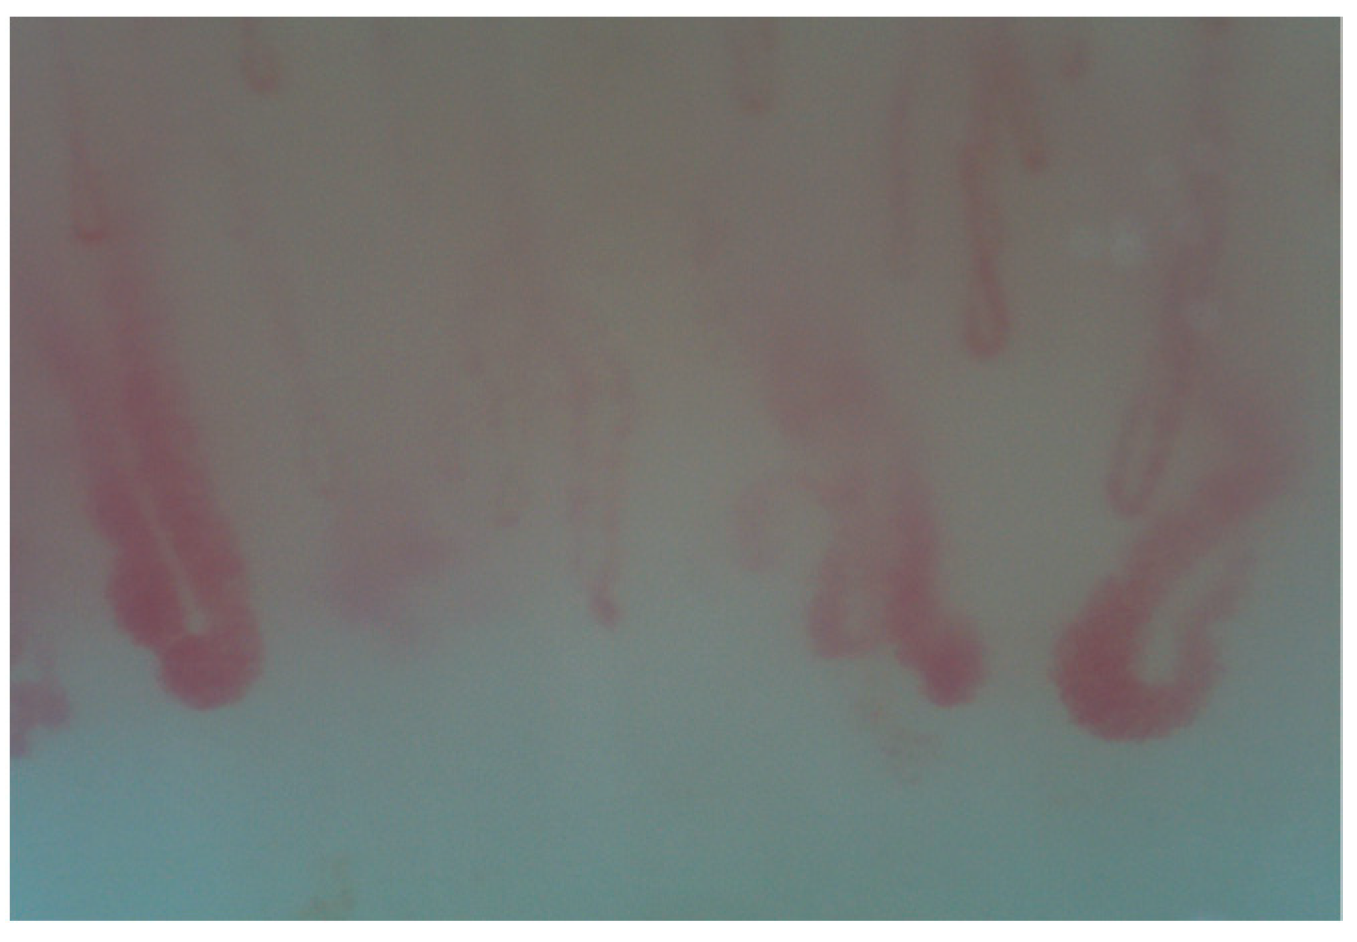

2. Normal Capillary Pattern